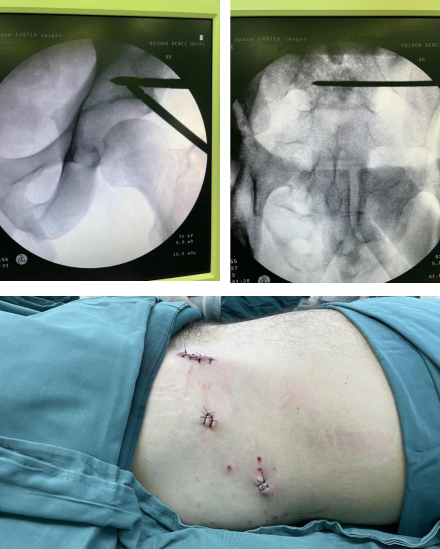

术中,于左侧股骨髁上置入骨牵引针,连接下肢牵引架。在C臂机透视下牵引左下肢撬拨复位,在天玑骨科机器人导航下置入固定左侧骶髂导针,透视见导针位置长短适中,螺钉固定,手术切口不到1公分。

然后在天玑骨科机器人导航下精准定位,使用骨盆前环infix内固定架固定,透视见位置及长短适中,再次行C型臂透视正侧位见骨折对位对线良好,螺钉位置以及长短均适中,整个手术1小时50分钟,通过三个小切口,顺利完成手术。

相较于传统的骨盆骨折手术而言,借助骨盆牵引床、骨盆微创复位系统所做的微创手术,术后一个半月左右,患者即可恢复正常生活。比传统手术恢复时间缩短一半。

目前患者术后恢复良好,再修养半个月左右就可以下地行走锻炼了。